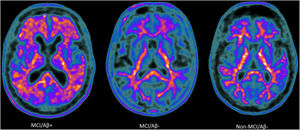

After complete evaluation of all study participants, 3 groups were established: group 1, elderly adults with MCI and suspected AD (MCI/Aβ+ group) (n=45); group 2, elderly adults with MCI and suspected non-AD pathology (MCI/Aβ− group) (n=59); and group 3, cognitively healthy elderly adults and with negative amyloid-PET results (non-MCI/Aβ− group) (n=60) (Fig. 1). All study participants signed informed consent forms. Ethical approval was obtained from the Ethics Committee of the University of Granada (reference # 2684/CEIH/2022).

Amyloid-PET scans ([18F]Florbetaben) of representative patients from each group: MCI/Aβ+ participant (left) showing intense amyloid burden in most cortical areas (positive finding); MCI/Aβ− (center) and non-MCI/Aβ− participants (right) showing normal uptake in the white matter (negative finding).